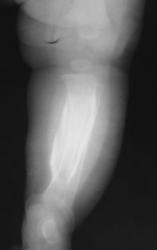

Ребенок 4 месяца. Отмечается увеличение размеров голени в течение нескольких месяцев после рождения. Травму, как бытовую, так и родовую мать отрицает. Мать обследована на ЗППП, в том числе сифилис. Выполнили рентгенографию, затем - КТ. Сначала думали о переломе и гипертрофической костной мозоли вследствие отсутствия иммобилизации, на реконструкции КТ видна как будто бы линия перелома (канал кровеносного сосуда?). Однако отсутствие положительной динамики со временем ("мозоль" не уменьшается) настораживает в плане возможной опухоли. Взяли открытую биопсию, материал пока еще в работе.

Уважаемый коллега! Еще раз пересмотрел изображения. И как это ни странно остался при первоначальном мнении, что это родовая травма. Возможно все-таки оказывалось какое-либо акушерское пособие? Все высказанное ранее - и "система", и сифилис полностью исключаются учитывая одностороннее поражение. В моей практике точно такого не было, но что-то подобное с меньшей "периостальной реакцией" было. Если предположить, что это неопластический процесс таких размеров, уже дико среагировала - бы кровь и другие показатели. С уважением Катенёв.

Данные по гистологии есть - они опубликованы на сайте радиография. Все много банальнее - гистологически изменения репаративного характера, т.е. - был перелом.

Опубликовано Валентин Катенёв в Сб, 01/24/2009 - 22:12. # Конечно, если-бы картинку обработать соответствующим образом, можно было-бы говорить более решительно, но на мой взгляд перелом не один, надо хорошо посмотреть дистальный метадиафиз. С большой степенью вероятности можно говорить о родовой травме. Интересно какое было предлежание плода и совершались-ли какие - либо акушерские мероприятия?

Опубликовано Валентин Катенёв в Сб, 01/24/2009 - 22:05. # Уважаемый коллега! Я совершенно не разбираюсь ни в КТ, ни в МРТ, ни в СКТ, ни в УЗИ. Но мне кажется, что в данном случае - см. вложение 11 четко дифференцируется косонаправленная прерывистость кортикального слоя б/берцовой кости - перелом? По всей видимости и гиперостоз и прочие изменения вызваны не диагностированным переломом.

Образование представлено компактной и губчатой костной тканью с прослойками рыхлой соединительной ткани, сосудами капиллярного типа, а также элементами костного мозга, которые представлены клеточными элементами эритроидного ряда. Признаков атипического роста не выявлено.

Заключение: учитывая морфологическую картину материала, данные клиники, рентгенологии, можно предположить репаративный характер данного процесса. Больному показано наблюдение в динамике.

По всей видимости, это все-таки недиагностированный перелом. Спасибо всем за комментарии.